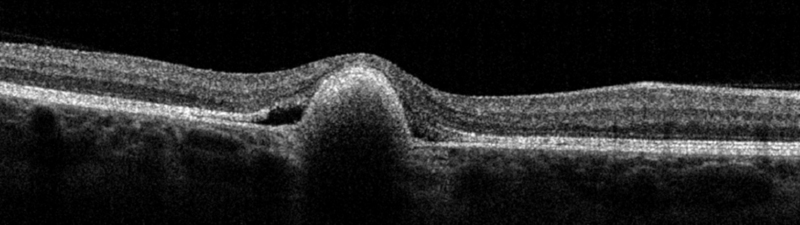

También obtuvimos imágenes de tomografía de coherencia óptica de madre e hija:

Figura 4a

Figura 4b.

Respuesta correcta: e

En la imagen de OCT de la hija (Figura 3a y Figura 3b) vemos una imagen hiperreflectiva por encima del EPR, más heterogénea en OD (estadio viteloruptivo) y fijándonos en la línea ESI ésta está integra en ambos ojos, no es el caso de la madre (Figura 4b) donde vemos una discontinuidad. La imagen de OCT del ojo derecho (Figura 4a) de la madre no muestra hallazgos patológicos.